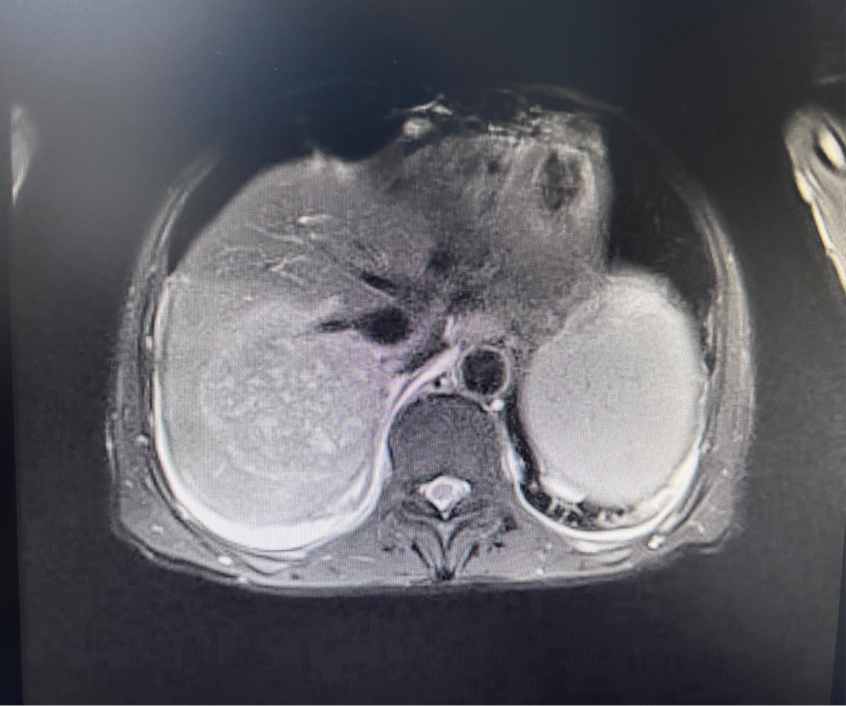

再度复查炎症指标,发现一路飙升了十几倍!床边彩超检查显示肝脏中存在“占位性”病变。这到底是怎么回事?究竟是入院前就有的病灶被大家遗漏了,还是住院期间新发的呢?

遵循外科意见,完善腹部CT后提示肝右叶上段占位性病灶,考虑肝脓肿可能性大。但特别的是,脓肿并未“完全成熟”,还不需要穿刺引流等手段,外科会诊后建议继续抗感染治疗,之后随诊复查脓肿变化,如果能自行吸收,就不需要手术穿刺。

图源:作者提供

仔细分析病情后可以推测,秦先生的肝脓肿是住院期间新发的概率极大,佐证原因之一就是脓肿还未成熟。原发感染部位在胃肠道,胃肠道的血液会汇入肝脏门静脉,病菌自然也“乘坐顺风车”定植在肝脏。